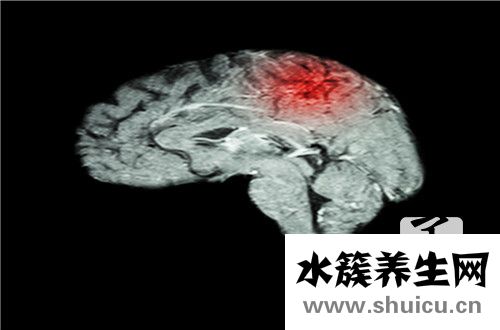

膠質瘤是對人體危害極大的顱內腫瘤。如果不幸患上神經膠質瘤,不僅會影響人體健康,還會影響正常的生活和工作,還會造成嚴重的心理壓力和經濟負擔。膠質瘤通常是原發性腦腫瘤。膠質瘤通常被分類。低度...

人體的許多器官都容易發生腫瘤,其中最嚴重的是頭部的顱內腫瘤。因為如果一個腫瘤發生在一個人的頭部,它將壓迫其他腦神經,并造成更嚴重的后果。顱內最嚴重的腫瘤是顱內動脈腫瘤,手術風險非常高。顱內...